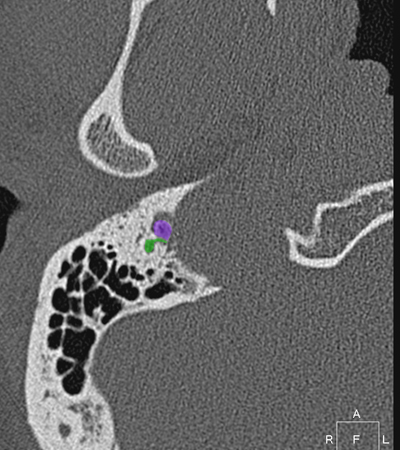

Radioanatomie du rocher sur coupes TDM

Différentes coupes de référence (A. Attyé 2013)

Coupe axiale passant par le canal semi-circulaire supérieur Coupe axiale passant par le canal semi-circulaire latéral Coupe axiale passant par le modiolus de la cochlée Coupe axiale passant par la fenêtre ronde Coupe axiale passant par le ganglion géniculé Coupe axiale passant par l'articulation incudo-malléaire Coupe axiale passant par la partie pétreuse de l'artère carotide interne Coupe axiale passant par le nerf tympanique

Coupe axiale passant par le foramen styloïde Coupe coronale passant par le muscle tenseur du tympan Coupe coronale passant par le recessus epitympanique Coupe sagittale passant par le segment mastoïdien du nerf facial coupe sagitalle oblique passant par le canal semi-circulaire supérieur (plan de Pöschl) Reconstruction axiale passant par le plan de l'étrier Coupe axiale passant par les apex pétreux